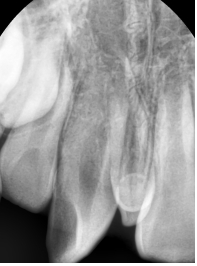

¾Õ´Ï°¡ ¹ú¾îÁö°í »ß¶Ô¾îÁ® Àִ ȯÀÚ¿¡¼ X-ray¸¦ ÃÔ¿µÇÏ¿´´õ´Ï °úÀ×Ä¡°¡ ¸Åº¹µÇ¾î ÀÖ´Â °ÍÀÌ º¸ÀÔ´Ï´Ù.

Ä¡¾Æ »Ñ¸® ¾ÕÂÊ¿¡ ¸Åº¹µÇ¾î ÀÖ´Â °úÀ×Ä¡·Î ÀÎÇØ ¾Õ´Ï »çÀ̰¡ ¹ú¾îÁö°í, ¿À¸¥ÂÊ ¾Õ´Ï°¡ »ß¶Ô¾îÁø ä·Î

¸ÍÃâÇÏ¿´½À´Ï´Ù.

¾Õ´Ï»çÀÌ¿¡ À§Ä¡ÇÑ °úÀ×Ä¡ ¶§¹®¿¡ ´Ù¸¥ Ä¡¾ÆµéÀÌ ¸ÍÃâÇÒ °ø°£ÀÌ ºÎÁ·ÇØÁ®¼ Ä¡¾Æ°¡ »ß¶Ô¾îÁ³½À´Ï´Ù.

ÀÌ·± °æ¿ì¿¡´Â °úÀ×Ä¡¸¦ »Ì¾Æµµ Ä¡¿ÀÌ ÀúÀý·Î °³¼±µÇÁö ¾Ê½À´Ï´Ù.

°úÀ×Ä¡¸¦ ¹ßÄ¡ÇÑ ÈÄ¿¡ ±³Á¤Ä¡·á¸¦ ÅëÇØ ¹®Á¦¸¦ ÇØ°áÇØÁÖ¾ú½À´Ï´Ù.